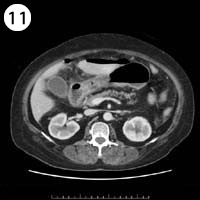

57歳 女性

単純CT

造影CT